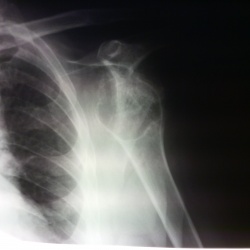

Принесли снимки на описание.Данных по старушке нет.